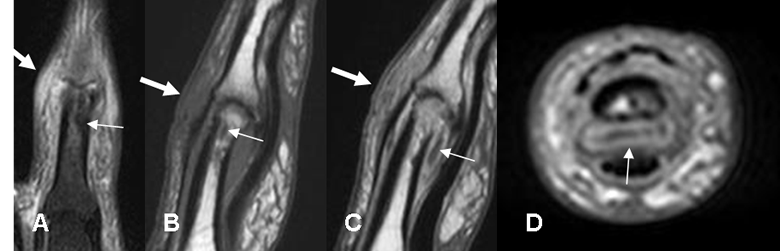

Fig 45 A. Osteomielitis crónica reagudizada.

A: RM coronal en STIR y B: RM sagital en T1. Igual paciente anterior. La imagen en la parte distal de la falange es hipointensa en todas las secuencias y no realza con el contraste, correspondiendo a fibrosis. (Flecha delgadas). Hay cambios inflamatorios de tejidos blandos hiperintensos en STIR e hipointensos en T1. (Flechas gruesas).

C: RM sagital y D: RM axial en T1 con contraste. Realce del contraste por los tejidos blandos (Flecha gruesa) y pequeña colección en la parte anterior cuyos bordes realzan, por osteomielitis crónica reagudizada. (Flechas delgadas).